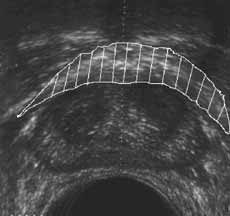

Рис. 13 и 14. (Слева) Фиброзно-мышечная строма предстательной железы. (Справа) Капсула предстательной железы.